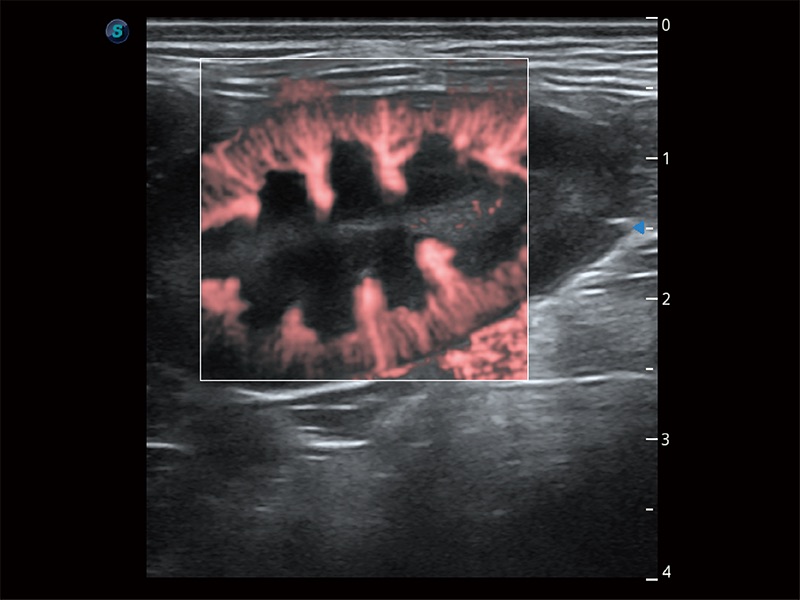

極大提升超低速微細(xì)血流的檢出能力,同時(shí)更精準(zhǔn)地濾除軟組織和超聲信號(hào),為獸用醫(yī)生提供以往無(wú)法通過(guò)常規(guī)血流獲得的疾病診斷信息。